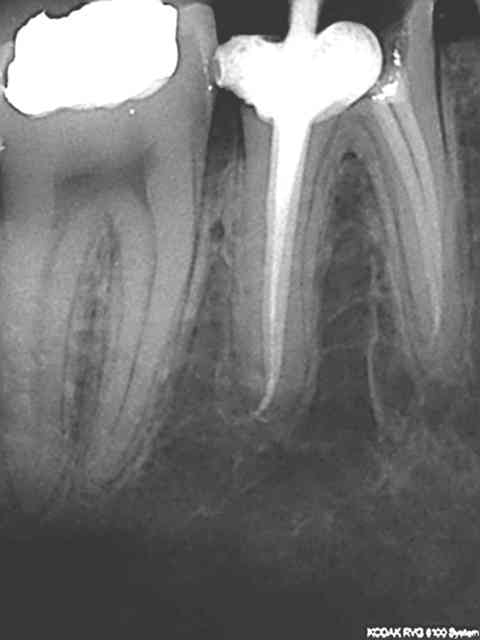

Exemples routiniers d'une banalité affligeante......

R24 kuiaas - Eugenol

R26 urwzsa - Eugenol

R8 q2dwjf - Eugenol

R14 d5xuv9 - Eugenol

Pepsi tmi4vp - Eugenol